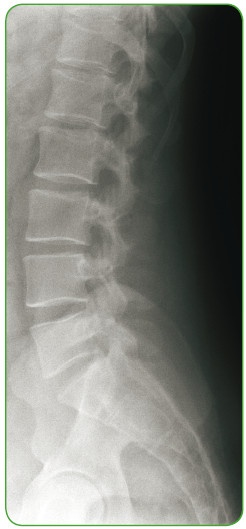

Иллюстрация к книге — Энциклопедия диагностики и лечения от А до Я [i_152.jpg]

Боковая рентгенограмма позвоночника